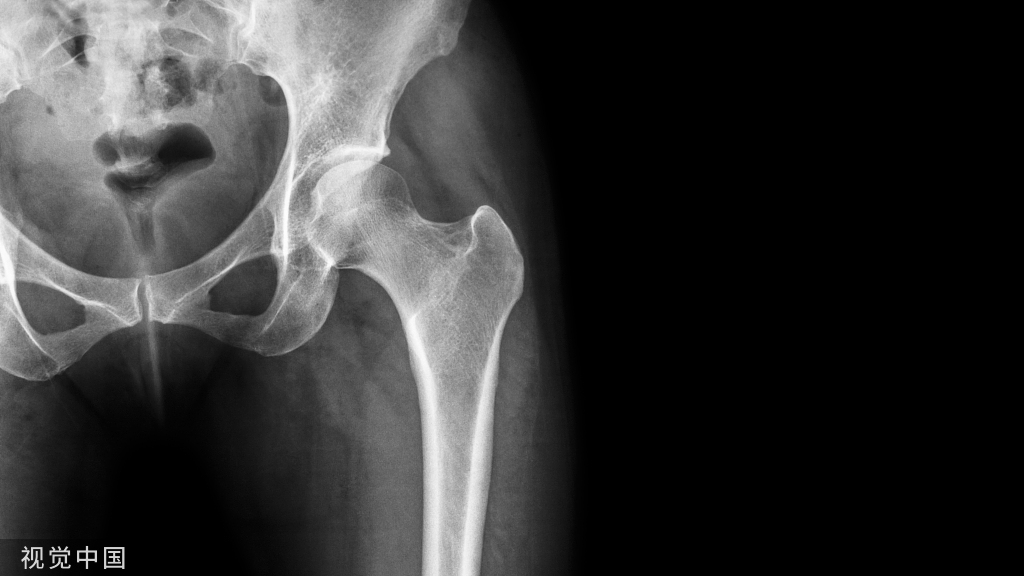

10股骨干应力性骨折

股骨干应力性骨折通常见于长跑运动员,该损伤与内收肌的反复牵拉有关,表现为运动时疼痛,过度剧烈活动可能导致粗隆下骨折,需早期干预避免骨不愈合及继发损伤。